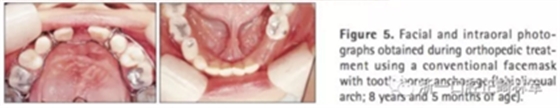

第二階段(圖5,6;表2)

面弓矯治包括在混合牙列及早期恒牙列的傳統(tǒng)牙支抗面弓及恒牙列的骨支抗面弓。由于患者曾行腭成形術(shù),為了將矯治力傳遞到上頜骨,使用唇舌弓而不是快擴。8歲5月時開始用面弓聯(lián)合唇舌弓矯治(500g/邊,與合平面呈30°向下),持續(xù)3年6月。患者佩戴時間為12-14時/天。